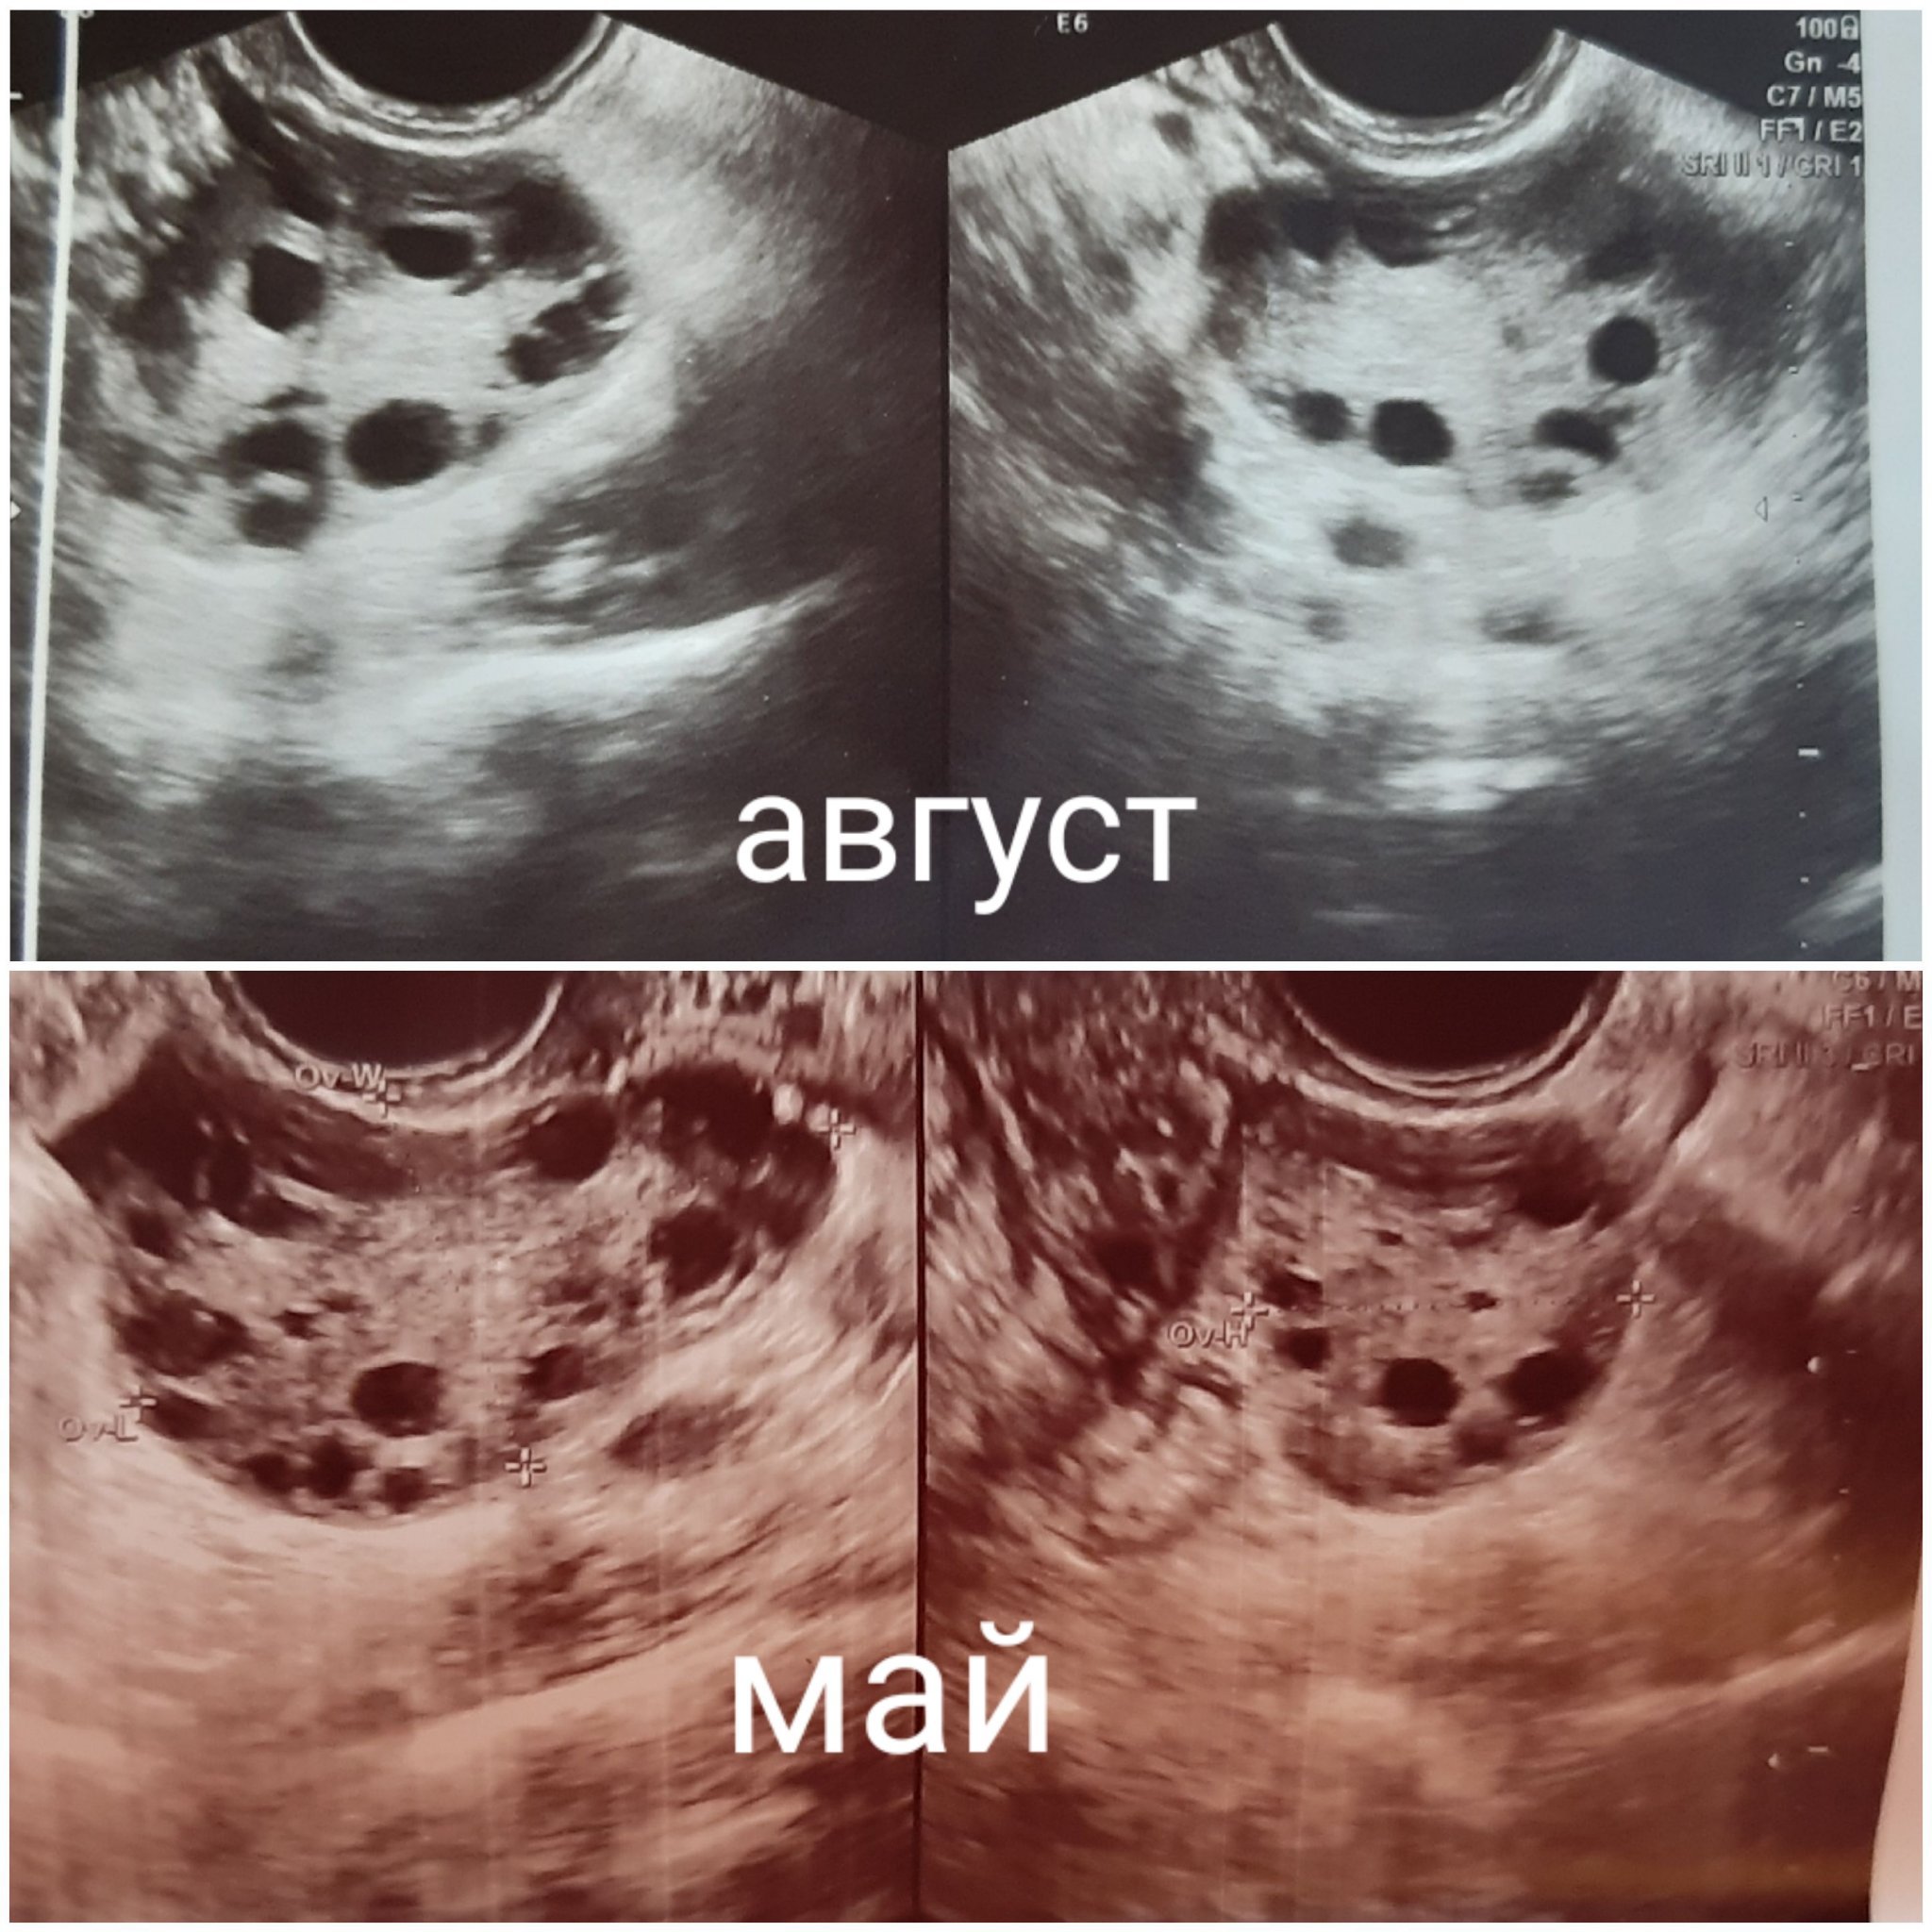

Най-често срещаните причини за проблеми със зачеването включват нередовен менструален цикъл, наднормено тегло, тютюнопушене, неправилно време на полов акт, поликистозни яйчници, инсулинова резистентност, възрастови фактори и други хормонални проблеми. Тези фактори могат да допринесат за трудностите при зачеване и поддържане на бременност.